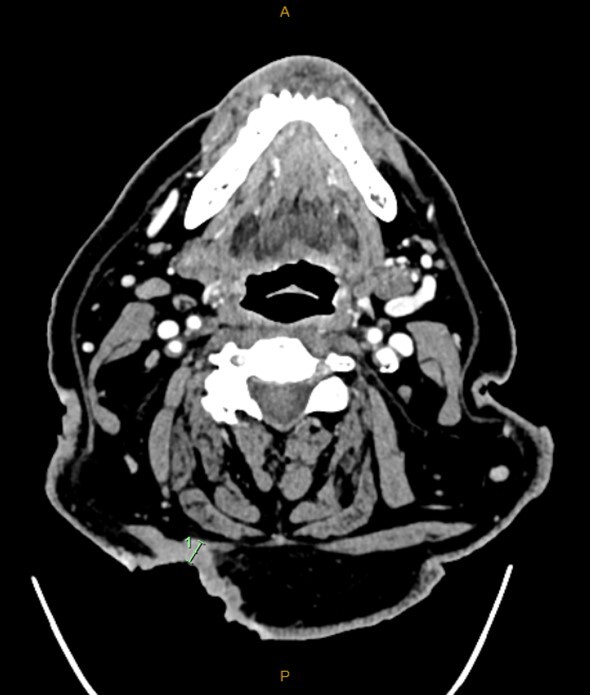

A computed tomography (CT) scan performed to evaluate the extent of the lesion showed the lesion invading the patient’s right splenius capitis and upper trapezius muscles (Figure 1). A radiographically suspicious level VB lymph node correlated with the examination findings, but it was difficult to ascertain whether this was contiguous or lymphovascular spread. Histology from a subsequent ultrasound-guided aspiration of this node was strongly suggestive of metastatic BCC.